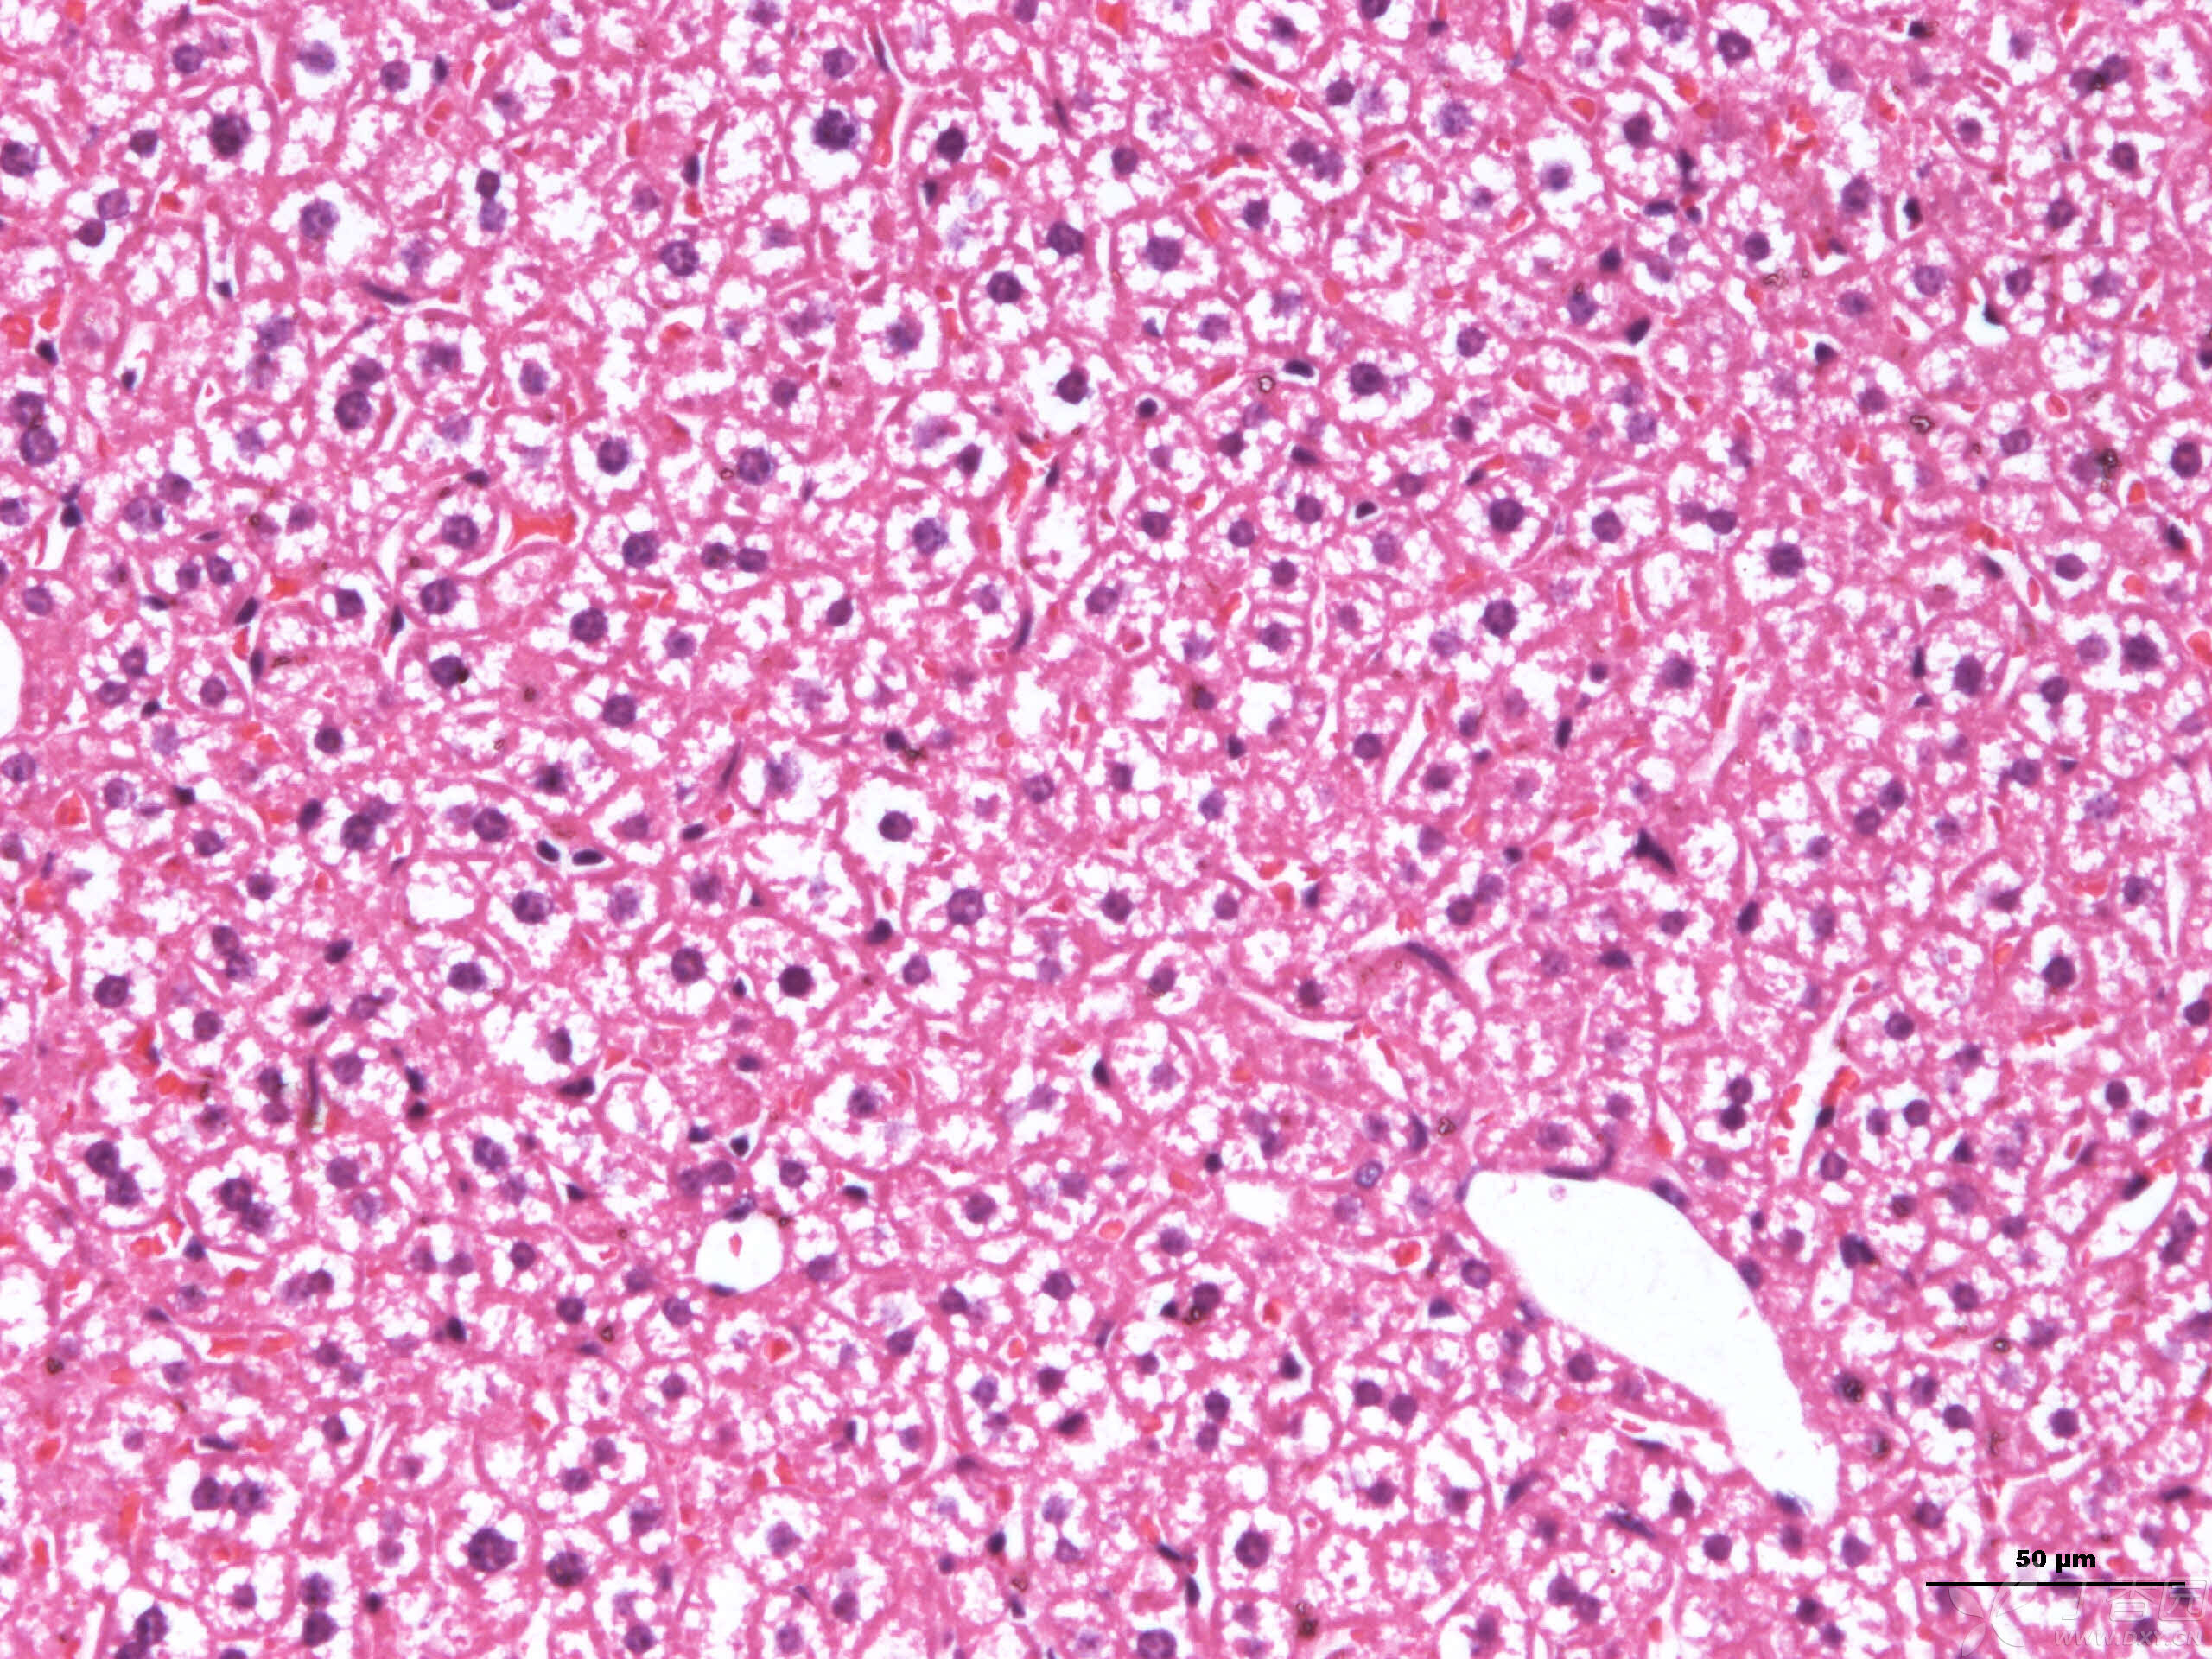

小鼠肝脏切片:深染的胞核是肝细胞核,还是肿瘤肝转移的?

【求助】小鼠正常肝脏he 染色图片

小鼠肝h&e染色图片,这些白色是脂肪变性或细胞肿胀吗?

关于小鼠肝脏病理切片的请教